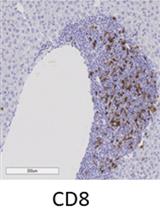

Representative data: